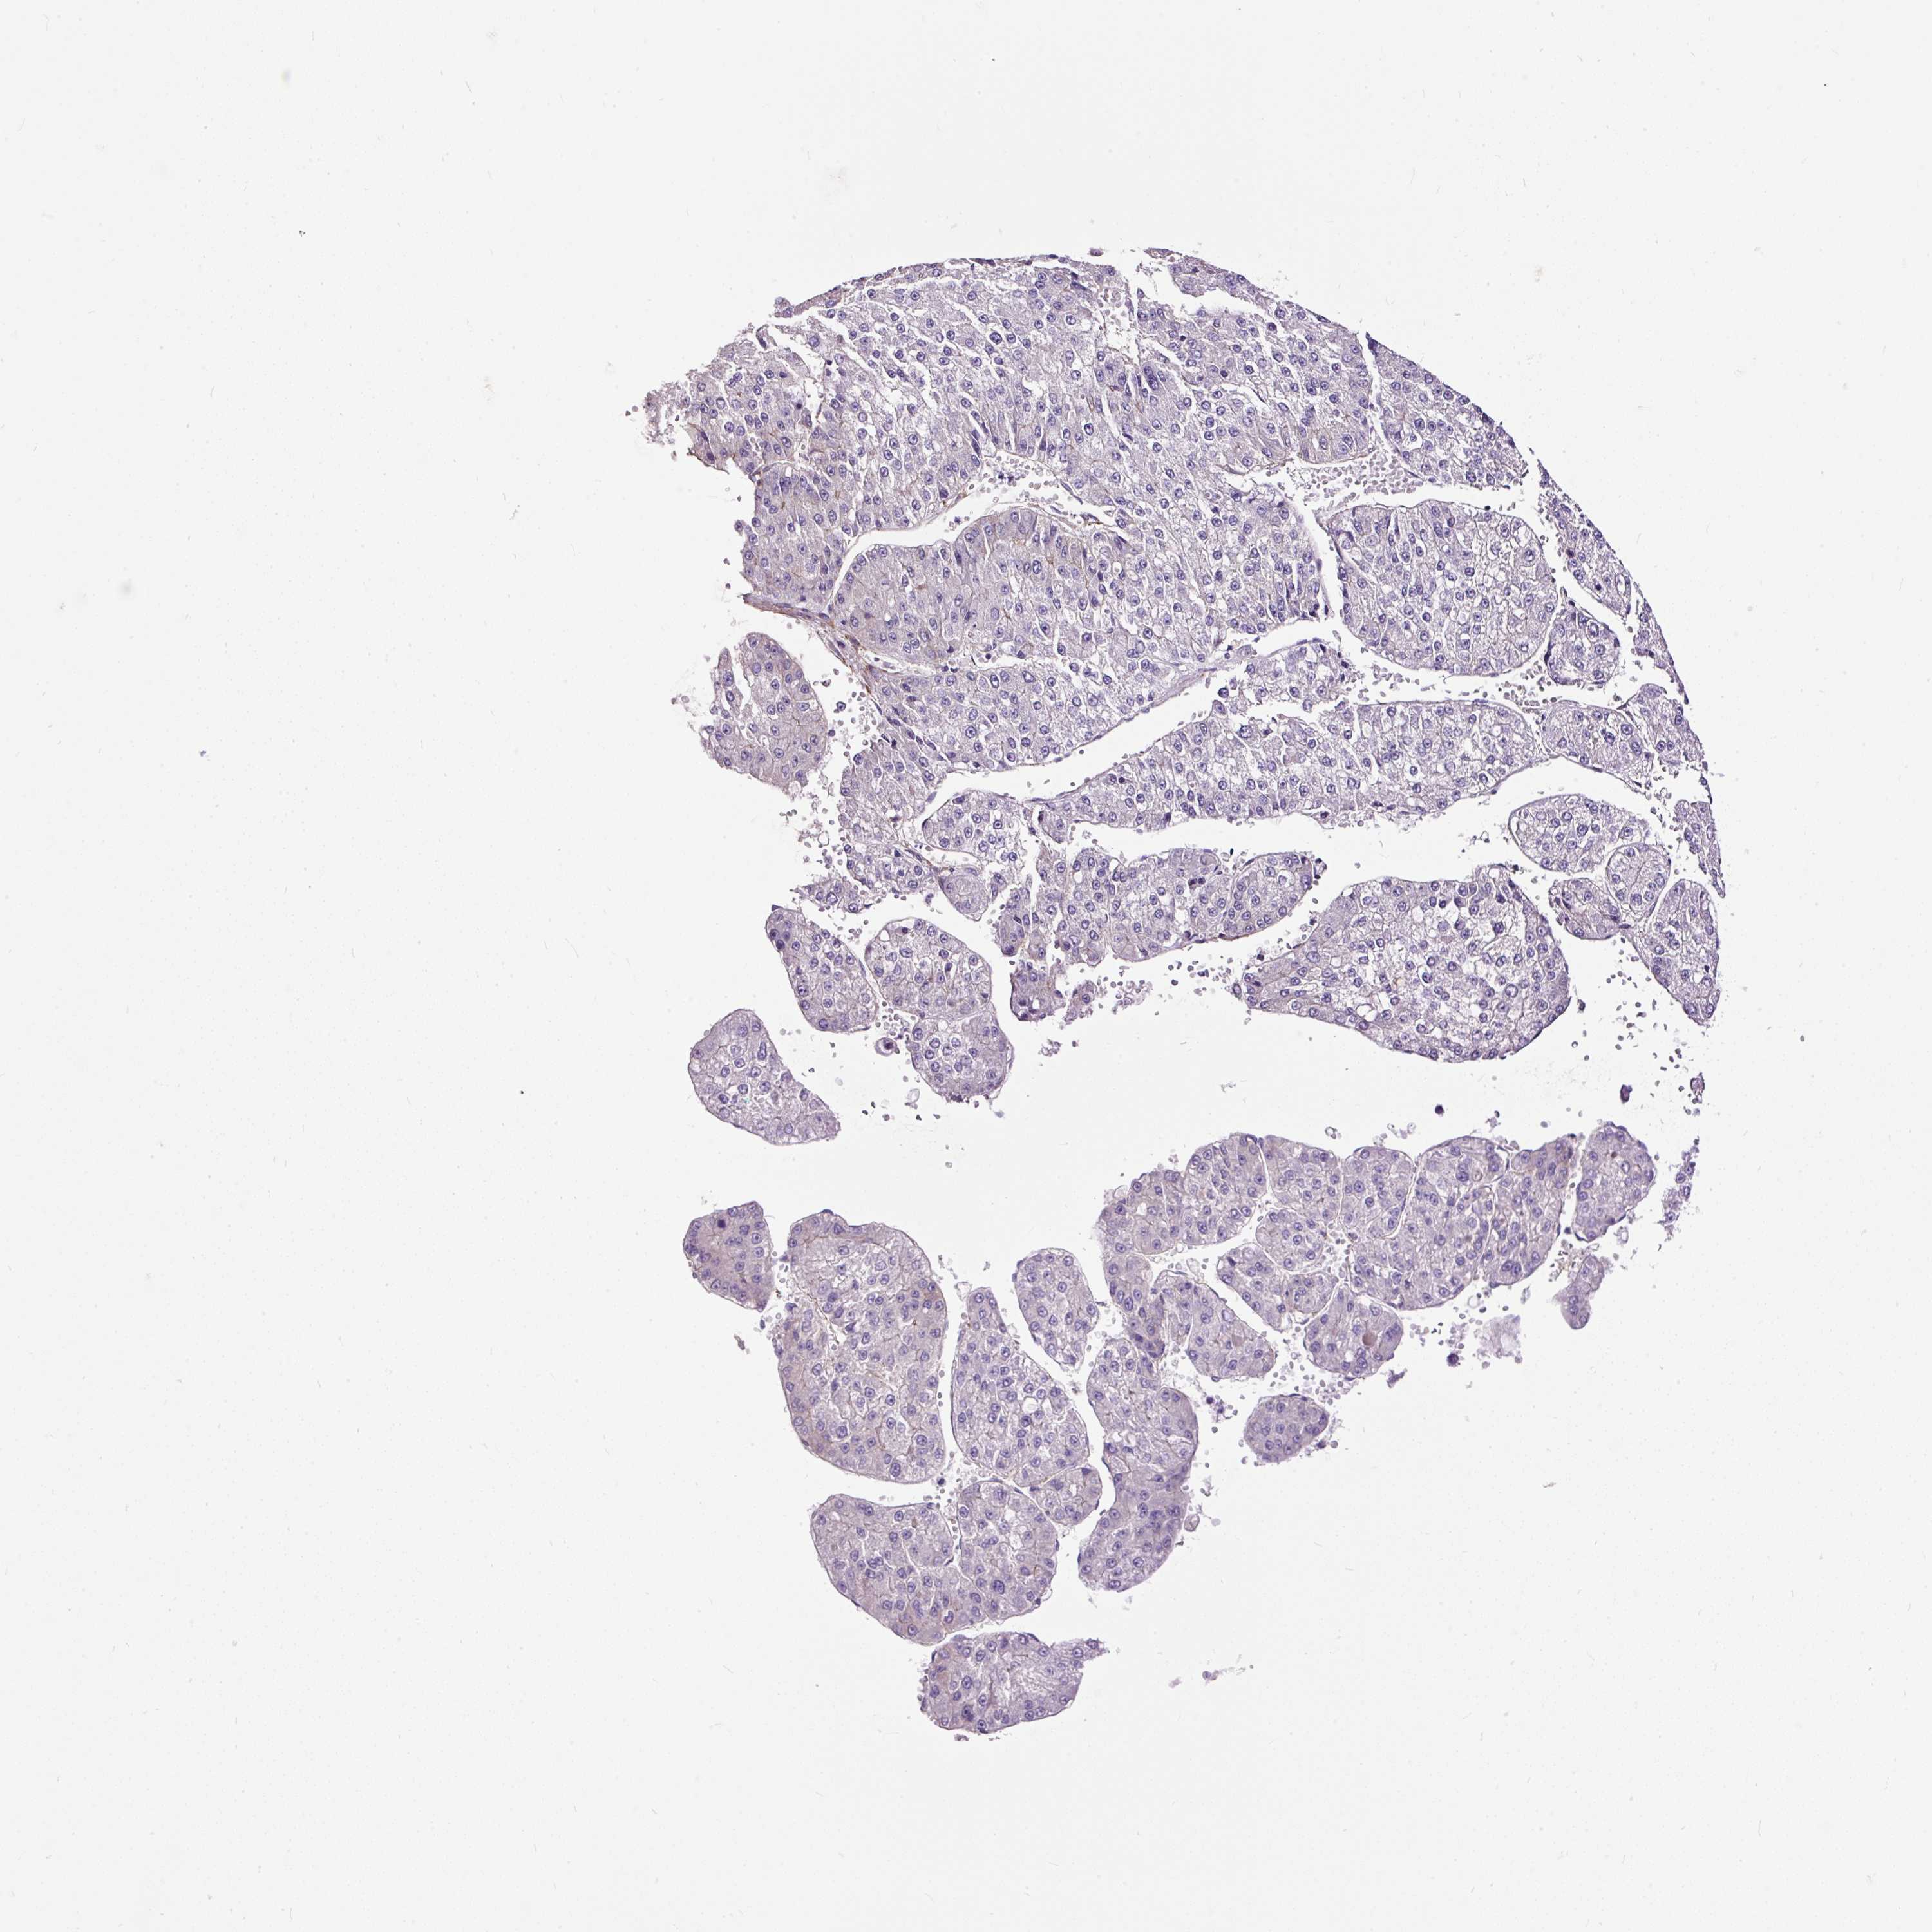

LIVER CANCER - Protein expressioni

A mouse-over function shows sample information and annotation data. Click on an image to view it in a full screen mode. Samples can be filtered based on level of antibody staining by selecting one or several of the following categories: high, medium, low and not detected. The assay and annotation is described here.

Note that samples used for immunohistochemistry by the Human Protein Atlas do not correspond to samples in the TCGA dataset.

Antibody stainingi

Antibody staining in the annotated cell types in the current human tissue is reported as not detected, low, medium, or high, based on conventional immunohistochemistry profiling in selected tissues. This score is based on the combination of the staining intensity and fraction of stained cells.

Each image is clickable and will lead to virtual microscopy that enables deeper exploration of all samples and also displays staining intensity scores, fraction scores and subcellular localization as well as patient and tissue information for each sample.

Antibody HPA055743

Staining

High

Medium

Low

Not detected

Intensity

Strong

Moderate

Weak

Negative

Quantity

>75%

75%-25%

<25%

None

Location

Nuclear

Cytoplasmic/membranous

Cytoplasmic/membranous,nuclear

Cholangiocarcinoma

Carcinoma, Hepatocellular, NOS